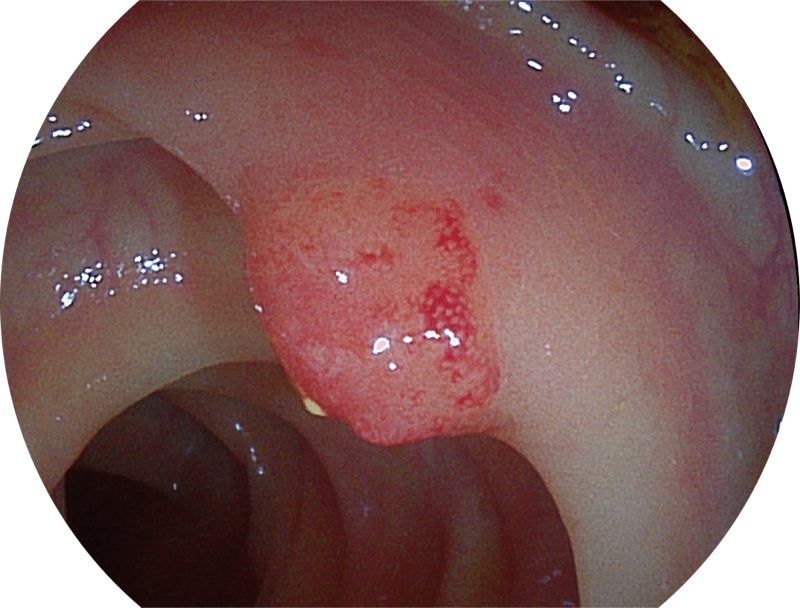

利用了血红蛋白在不同波长吸收下系数不同的原理,设计的一种光学域滤波和数字域滤波结合的染色技术,既保证了图像亮度,又可增强黏膜血管的对比度,充分凸显早期病变的细微结构变化,为临床疾病的观察诊断提供更丰富的参考信息。

(Versatile Intelligent Staining Technology)